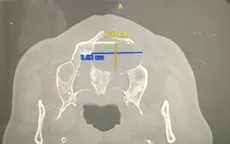

Bóc nang xương hàm gây chảy dịch mũi cho bệnh nhân VTV.vn - Bệnh viện Đa khoa Xuyên Á Long An vừa phẫu thuật cho 2 bệnh nhân bị nang xương hàm trên.

Nang xương hàm do bọc răng thẩm mỹ VTV.vn - Bệnh viện Đa khoa tỉnh Bắc Giang vừa tiếp nhận điều trị cho một bệnh nhân bị nang xương hàm trên.

Bé 12 tuổi phải nhập viện vì biến chứng nang xương hàm VTV.vn - Bệnh viện đa khoa Hùng Vương (Phú Thọ) vừa tiếp nhận điều trị cho một bệnh nhi 12 tuổi bị nang xương hàm.